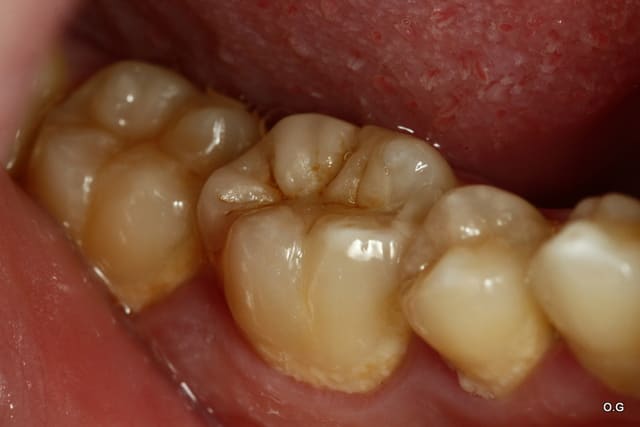

Onlay emax à 5 ans... contrôle la semaine dernière...

Dans cette situation, que donnerait un composite ?

tiens c'est bizarre , sur la dernière photo de cingulum (magnifique travail d'ailleurs) , la dent est toujours sur l'arcade alors que le joint semble être juxta voir sous gingival. Il m'a semblé avoir lu plus haut qu'un joint en compo ça se carie automatiquement au bout de cinq ans....

Allez cingulum , arrête de nous faire marcher, fais peter la radio avec la reprise de carie, l'endo, l'IC et la CCM!